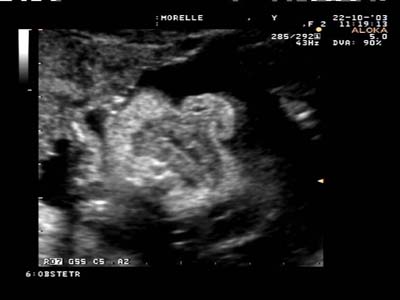

Lèvre supérieure continue